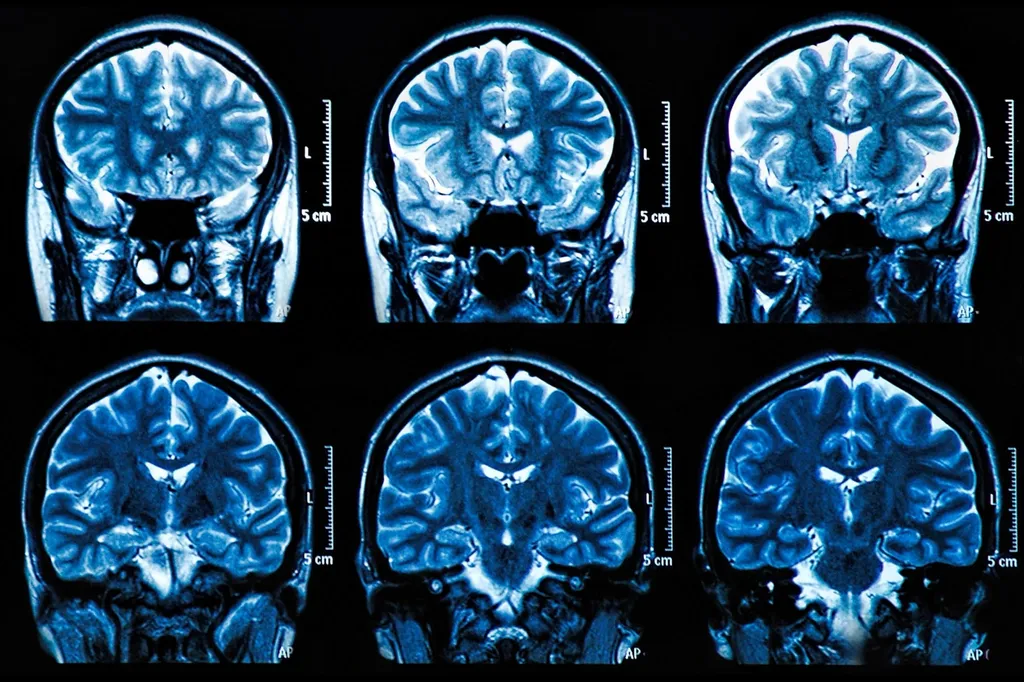

MRI Brain Scan Neuroscience Images

“目前,診斷阿爾茨海默病需要神經成像,”皮特大學精神病學助理教授、資深作者Thomas Karikari博士說?!斑@些檢查很昂貴,需要很長時間來安排,即使在美國,許多患者也無法使用核磁共振成像和PET掃描儀。可訪問性是一個主要問題?!?/p>

目前,為了診斷阿爾茨海默病,臨床醫生使用了美國國家老齡化研究所和阿爾茨海默病協會在2011年制定的指南。該指南被稱為AT(N)框架,要求通過成像或分析腦脊液樣本檢測阿爾茨海默病病理的三個不同組成部分:淀粉樣斑塊的存在、tau纏結和大腦中的神經退行性變。